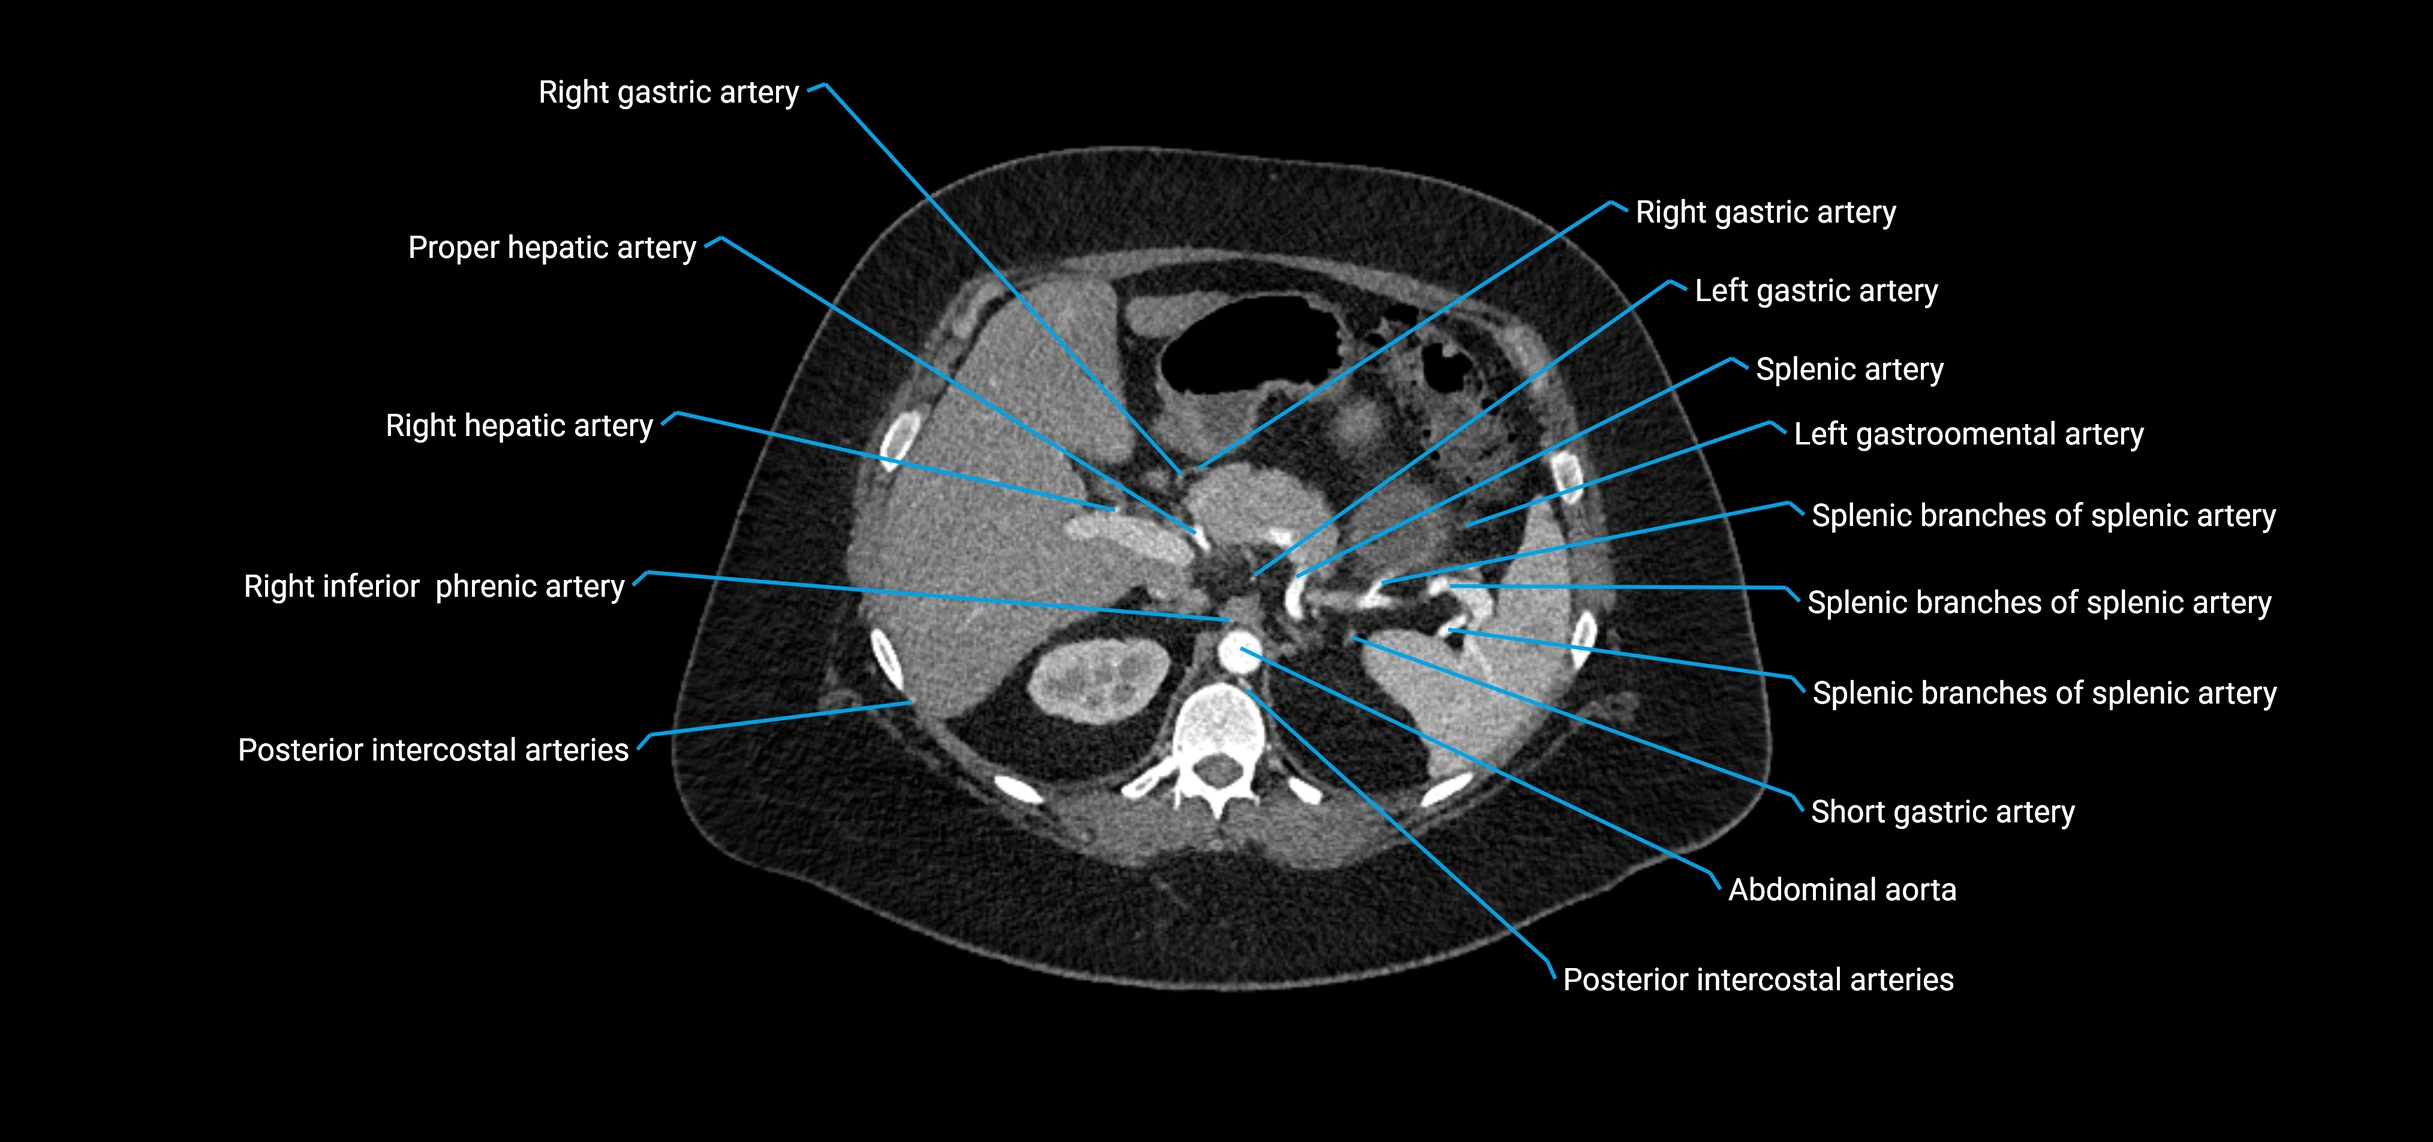

Contrast-enhanced CT (CTA):

• Gold standard for abdominal aortic imaging

• Provides excellent detail of lumen, wall, aneurysm, thrombus, and branch vessels

• Multiplanar and 3D reconstructions help in aneurysm measurement, stent graft planning, and dissection evaluation

• Detects acute rupture, traumatic injury, or occlusion with high sensitivity